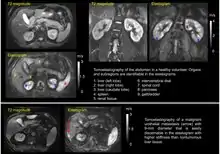

Tomoelastography requires external driver systems, which can efficiently generate shear waves throughout the entire field of view including tissues deep within the body. Multiple drivers can be combined such that waves propagate from the surface into the body from different directions to enable full illumination of larger regions with shear waves. Tomoelastography often employs mechanical vibrations at several driving frequencies for multifrequency wave analysis in order to stabilize inverse problem solutions for viscoelasticity reconstructions. A standard way of multifrequency viscoelasticity reconstruction is based on phase gradient analysis of plane waves[5] whereas other methods employ solutions of the Helmholtz equation.[6][7][8] The feasibility of tomoelastography was first demonstrated in the human abdomen using multifrequency MRE, where it was possible for the first time to display stiffness values (quantified as shear wave speed in m/s) across the entire axial MRI slice.[5] Although the elastograms are quantitative maps, tomoelastography images, like other radiological images, are often presented in standard gray-scale which gives more perceptual contrast to the subtle nuances than the color-scale.

Currently, most applications of tomoelastography are based on MRI, which is why tomoelastography is often referred to as an advanced MRE technique. Multifrequency-MRE based tomoelastography has been used for the diagnosis of diffuse liver disease,[9][10][11] renal diseases such as renal allograft dysfunction,[12] lupus nephritis,[13] and immunoglobulin A nephropathy (IgAN).[14] In addition, tomoelastography has been used for cancer imaging. In the liver, viscoelastic parameters of lesions less than 1 cm in diameter could be quantified for diagnostic purposes.[15] Pancreatic cancer has been shown to be abnormally stiff compared to surrounding tissue, resulting in a large tumor contrast in elastograms.[16][17] In the prostate, tomoelastography has been able to distinguish cancer from benign lesions.[18]